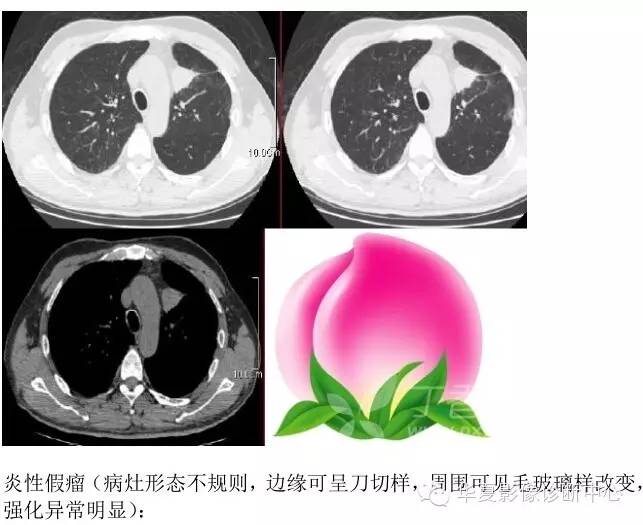

10、桃尖征 医学百科网 | YxBaike.Com

指肿块某一边缘尖角状突起形似桃尖,是肺炎性假瘤包膜的粘连牵拉,为良性肿块炎性假瘤特有。 医学百科网 | YxBaike.Com

医学百科网 | YxBaike.Com